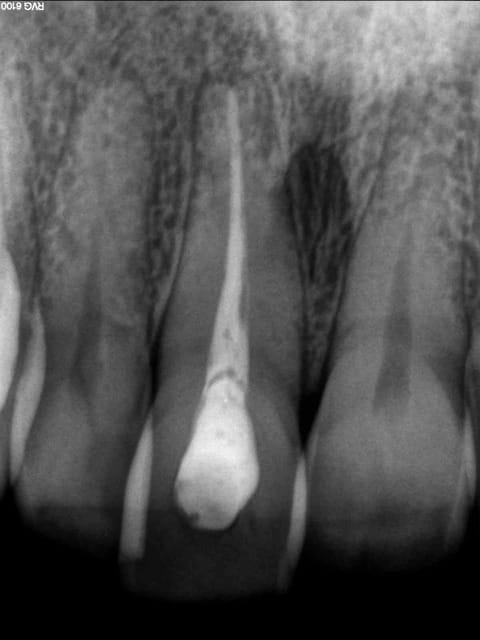

J'aimerais effectuer un éclaircissement interne sur une 11 traitée et dyschromiée avec le temps chez cette patiente sympathique et intéressée par le traitement. Je n'en ai jamais réalisé auparavant. Je me suis renseigné mais j'aimerais connaitre votre avis.